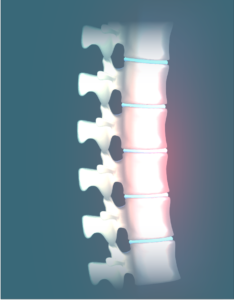

Herniated Disc

Herniated disc is a condition in which the outer fibers (annulus) of the intervertebral disc are damaged causing the soft inner material of the nucleus…

Lumbar Disc Herniation

Lumbar disc herniation is the most common cause of low back pain and leg pain (sciatica). The lumbar intervertebral discs are flat and round.